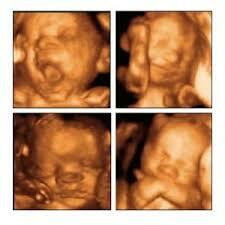

• 10º Semana

10º Semana

El feto desarrolla la capacidad de abrir la boca.

• 21º Semana

21º Semana

El feto engorda (sobretodo aumenta su grasa subcutánea)

• 14º Semana

14º Semana

Comienza el desarrollo de las extremidades.